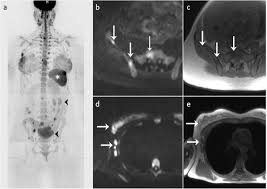

They might be at higher risk due to having family members with cancer or because they have certain gene abnormalities (mutations). By comparison, only 11 out of 48 patients, or 23 percent, with all fatty hilum in place had cancer. Because the dye can affect the kidneys, your doctor may. Unlike traditional forms of breast cancer, inflammatory breast cancers do not develop unusual lumps within the affected breast. Magnetic resonance imaging (mri) of the breast — or breast mri — is a test used to detect breast cancer and other abnormalities in the breast. Mri of breast can help breast cancer diagnosis. When women undergo mris to check for breast cancer, the scans sometimes reveal suspicious masses elsewhere in the body, which can generate a lot of anxiety and require more testing. This means that the test finds a mass or other change that seems to show cancer but it is not cancer. A breast mri is a highly effective test. Palpation of benign breast masses. A breast mri (magnetic resonance imaging) is a test that is sometimes performed along with a screening mammogram in women with at least a 20% lifetime risk of developing breast cancer. You may notice dimpling or pitting, and the skin on your breast. Some benign conditions such as fibrocystic disease can look like cancer.

An mri can help find a disease of the lungs or show tumors (growths) in the chest. But not every woman who has been diagnosed with breast cancer needs a breast mri. The features of a malignant breast condition on mri scan are often to do with the outer irregular borders of a lesion. A rash isn't the only visual symptom of inflammatory breast cancer. Any area that does not look like normal tissue is a possible cause for concern. A breast mri scan might also be used to assess the size of the cancer to check which kind of surgery is possible. They work to destroy the tumor or slow down the growth of cancer cells. This appears most commonly as streaking, known as linear enhancement. On the flip side, there are benign (not cancerous) breast changes which can mimic breast cancer as well. This means that the test finds a mass or other change that seems to show cancer but it is not cancer. Breast mri images are combined, using a computer, to create detailed pictures. What does breast cancer look like on a mammogram? The dye collection in the breast can also look clumpy or appear in a section of the breast, depending on the involvement of dcis.